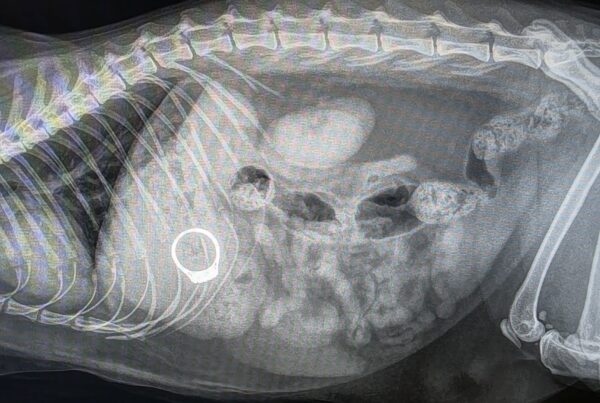

Lula’s Remarkable Recovery After a Severe Stick Injury